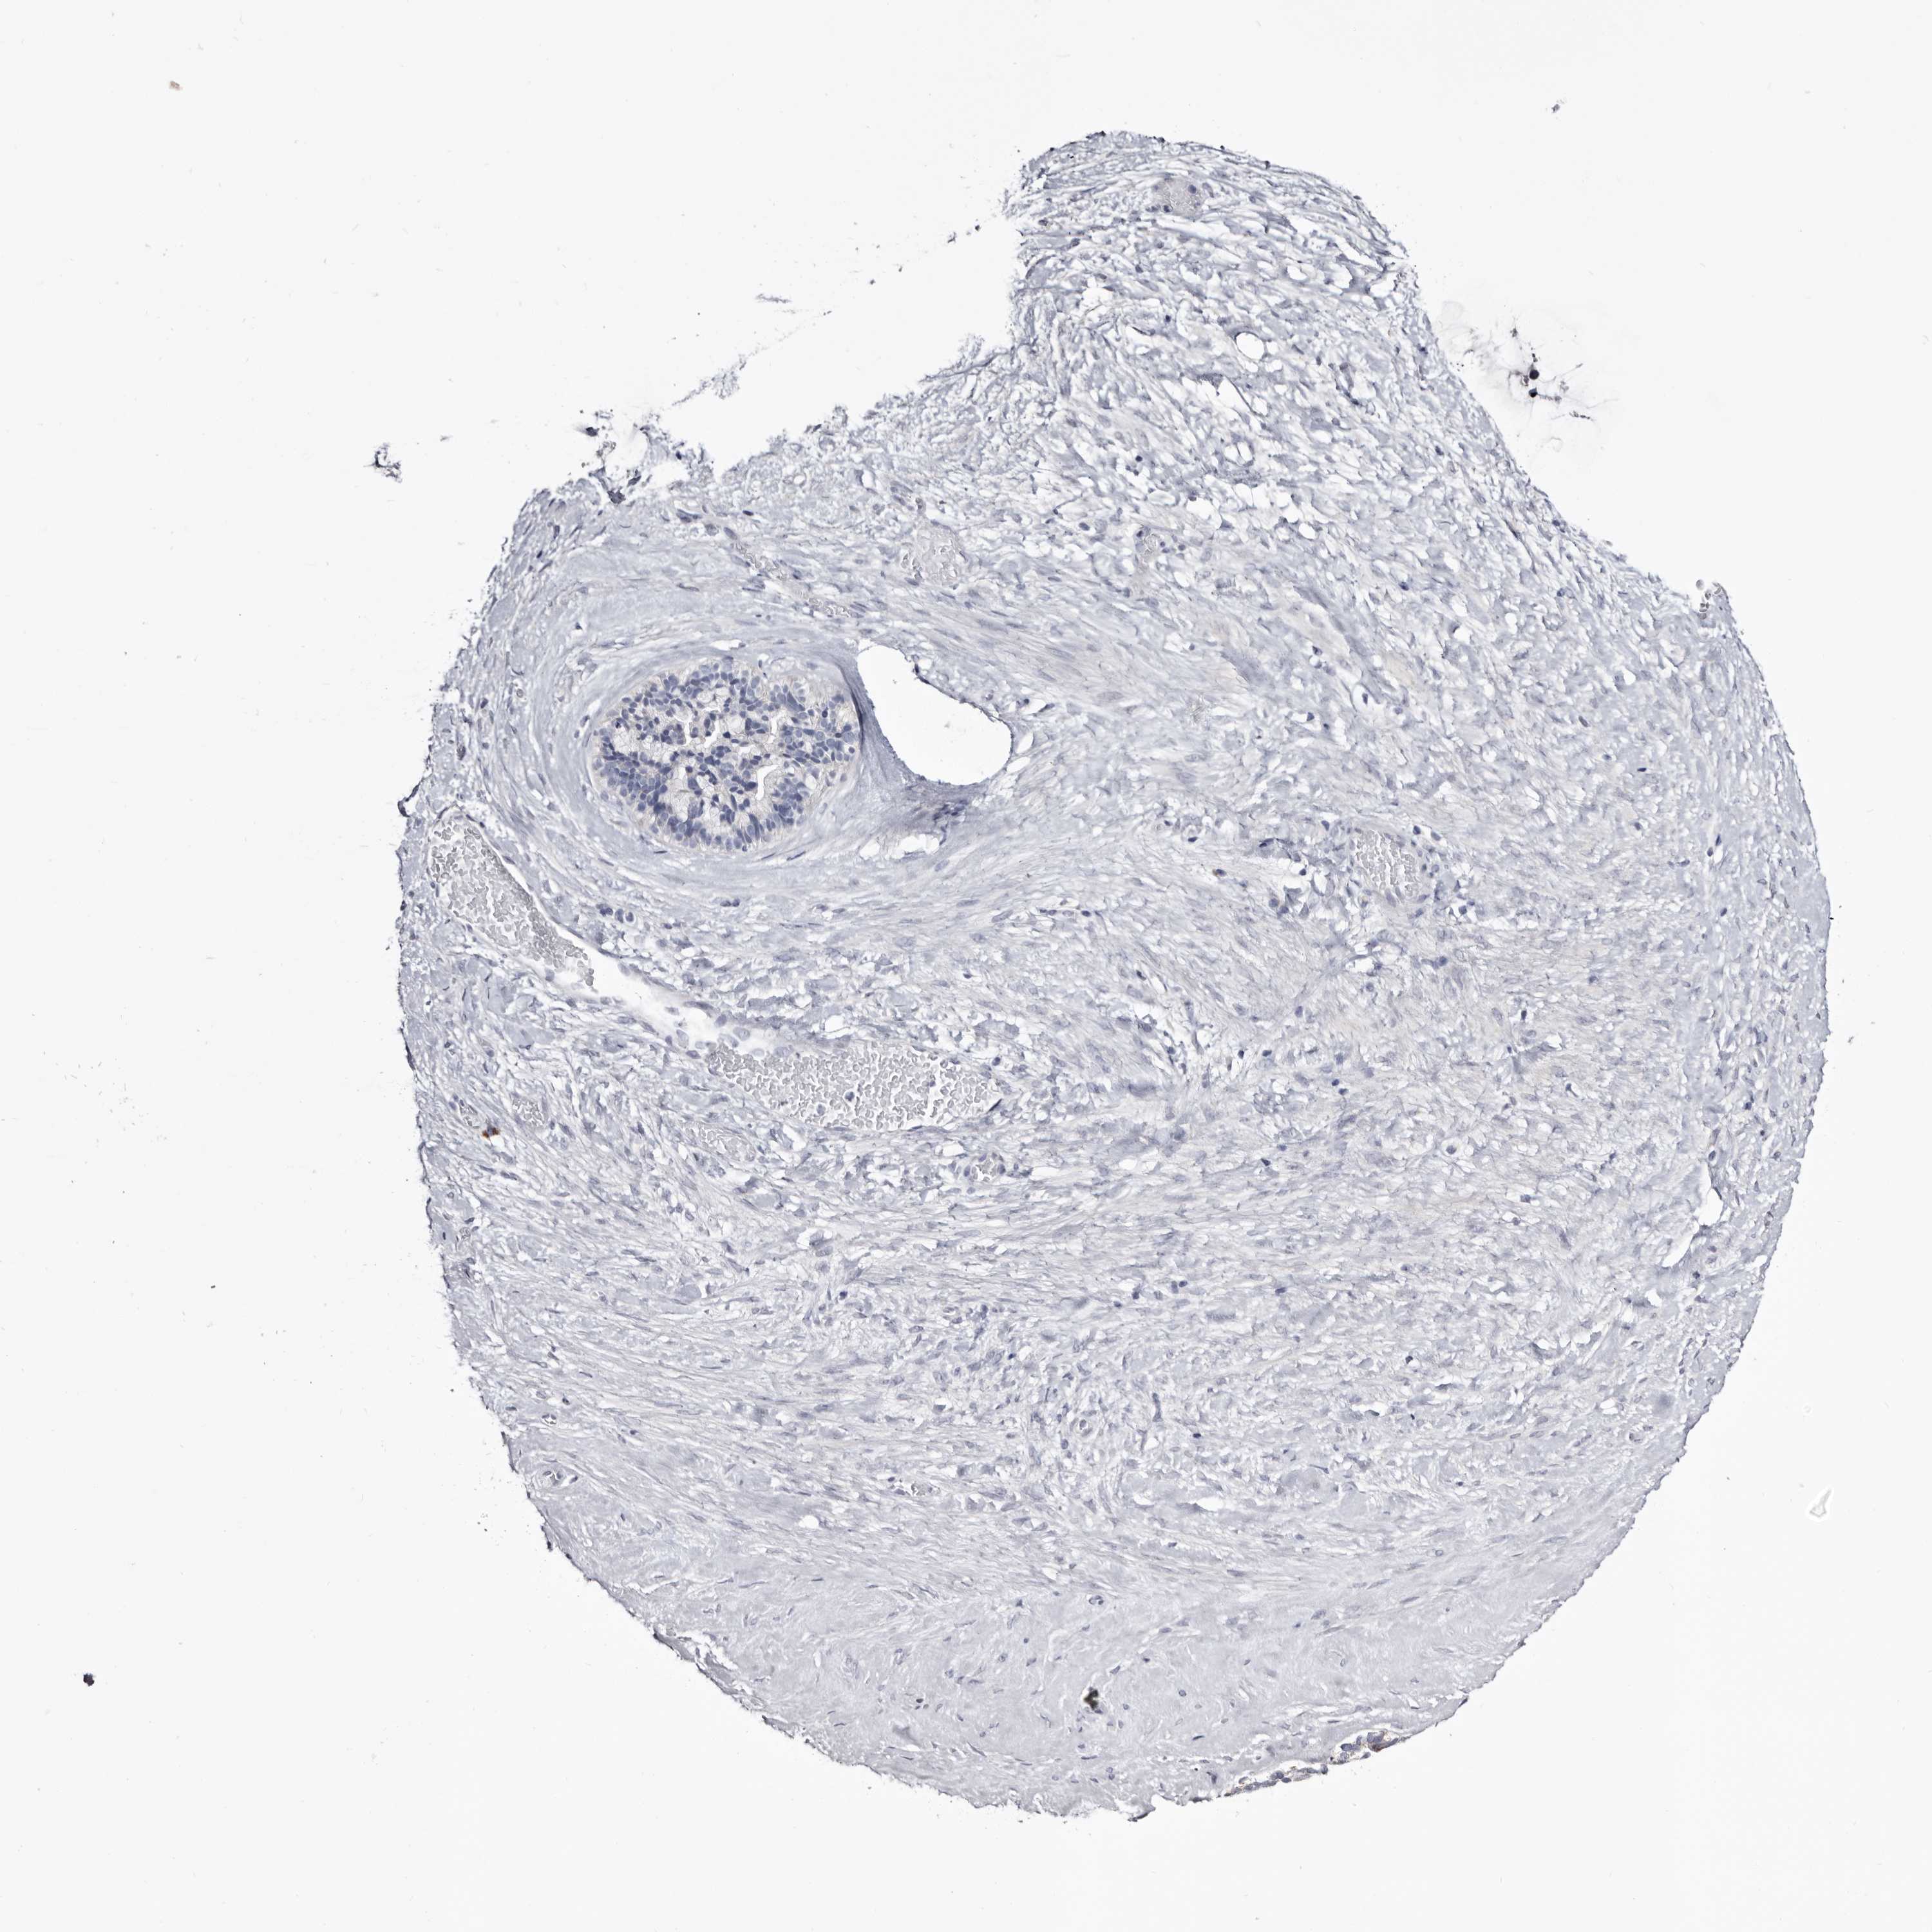

OVARIAN CANCER - Protein expressioni

A mouse-over function shows sample information and annotation data. Click on an image to view it in a full screen mode. Samples can be filtered based on level of antibody staining by selecting one or several of the following categories: high, medium, low and not detected. The assay and annotation is described here.

Note that samples used for immunohistochemistry by the Human Protein Atlas do not correspond to samples in the TCGA dataset.

Antibody stainingi

Antibody staining in the annotated cell types in the current human tissue is reported as not detected, low, medium, or high, based on conventional immunohistochemistry profiling in selected tissues. This score is based on the combination of the staining intensity and fraction of stained cells.

Each image is clickable and will lead to virtual microscopy that enables deeper exploration of all samples and also displays staining intensity scores, fraction scores and subcellular localization as well as patient and tissue information for each sample.

Antibody HPA007845

Antibody HPA026823

Antibody CAB015170

Cystadenocarcinoma, serous, NOS

Carcinoma, endometroid

Cystadenocarcinoma, mucinous, NOS

Carcinoma, NOS